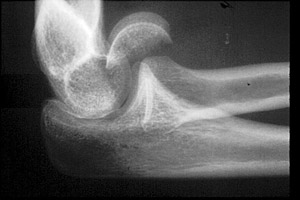

Capitellum Fracture

Fractures of the capitellum are the result of direct trauma to the extremity. In pediatric patients, this site is the second most common site of injury about the elbow.

- Click on the image for a larger versionALateral radiograph of the elbow. This demonstrates a fracture of the capitellum.